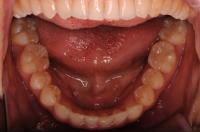

下の歯の治療は終わったんだけど、後は上の歯を並べながらかみ合わせも治療していくんだって。